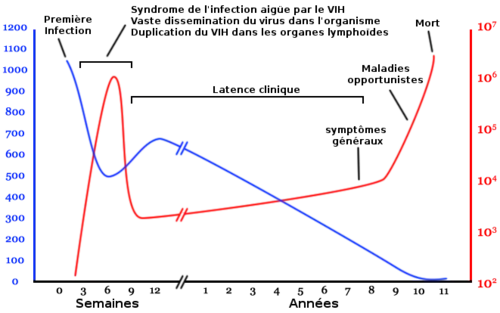

L'infection par le VIH évolue en plusieurs phases pouvant se succéder dans le temps :

- la primo-infection avec (50 à 75 % des cas) ou sans symptômes, phase de séroconversion qui suit la contamination ;

- une phase de latence, parfois accompagnée d'un état de lymphadénopathie généralisée ;

- une phase à symptômes mineurs de l'infection à virus de l'immunodéficience humaine ;

- la phase d'immunodépression profonde, ou stade de sida généralement symptomatique.

Dès la primo-infection, le virus se réplique activement dans l'organisme, avec une production quotidienne de dix milliards de virions, entraînant la destruction d'environ cinq milliards de lymphocytes T CD4+[103]. Cette réplication se stabilise, après quelques semaines, à un niveau plus ou moins important selon les sujets. Le système immunitaire, hyperactivé, compense partiellement la destruction massive des lymphocytes T CD4+ en augmentant leur production, mais l'infection à VIH persiste malgré tout, avec pour conséquence l'émergence et la sélection de virus mutants qui échappent à la réponse immunitaire de l'hôte.

Pendant plusieurs années, les lymphocytes T CD4+ semblent se renouveler rapidement malgré leur destruction par le virus, jusqu’à ce que l'épuisement des organes lymphoïdes centraux (thymus) ne permette plus leur régénération. La destruction des lymphocytes T CD4+ est bien souvent due à l'hyperactivation de ces cellules, par interaction avec certaines structures du virus, et non à une destruction directe par le VIH[103]. Après dix à quinze ans d'évolution spontanée sans traitement, le sujet est immunodéprimé (stade sida), des pathologies infectieuses ou tumorales rares (dites opportunistes) surviennent et conduisent au décès. Actuellement les traitements antirétroviraux évitent ou retardent l'évolution vers le stade sida, en maintenant les niveaux de réplication du virus au plus bas possible[103].

La destruction du système immunitaire et la progression clinique avec apparition de maladies opportunistes sont directement liées au taux sanguin des lymphocytes T CD4+ du patient[105]. L'efficacité des traitements antirétroviraux est évaluée par le niveau de réplication virale mesurée par la charge virale VIH (taux d'ARN plasmatique), la mesure de taux de lymphocytes T CD4+ (immunodepression) et par l'état clinique du patient.